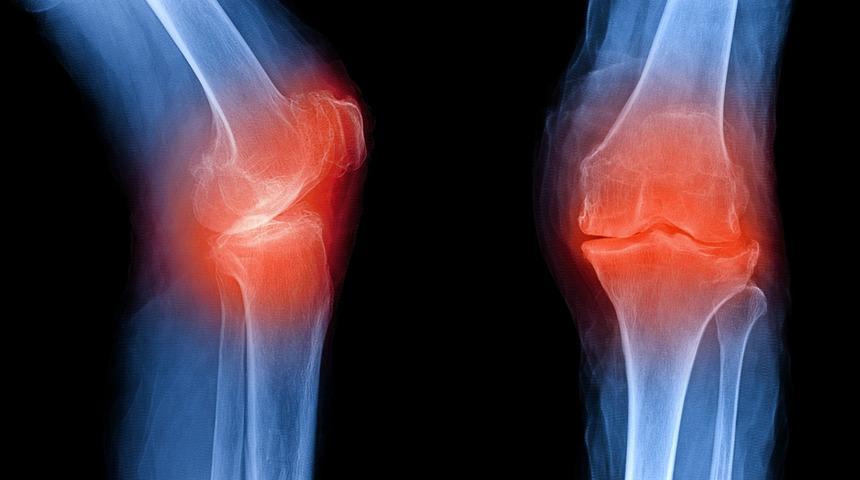

Diz eklemi, genişliği ve kıkırdak yüzeyi bakımından insan vücudunun en büyük eklemidir. Çok sık karşılaşılan kireçlenme türlerinden biri de dizlerde görülür.

Merdiven inip çıkma ile başlayan ağrı belirtisi, giderek istirahat halinde de hissedilmeye başlar. Zamanla diz çevresinde şişlik, takılma ve kilitlenme gibi sorunlar da ağrılara eşlik eder. Fazla kilonuz var ise, bir an önce kontrol altına almanız gereken bir durum olan diz kireçlenmesi, sosyal hayatınızı olumsuz yönde etkileyen sonuçlar doğurabilir.